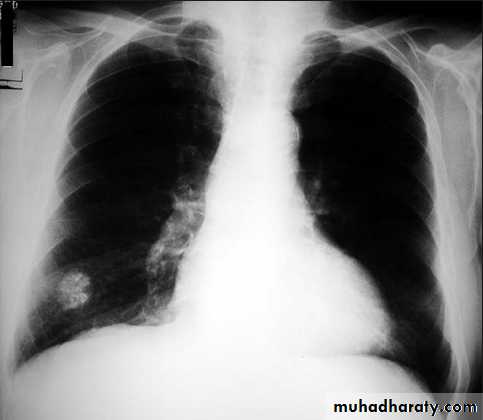

•Nodular (coin) lesion in the left upper lung with irregular edge (most probably cancinoma

Chest X-ray shows radio-opaque (white) nodular lesion in the right mid-lung field.